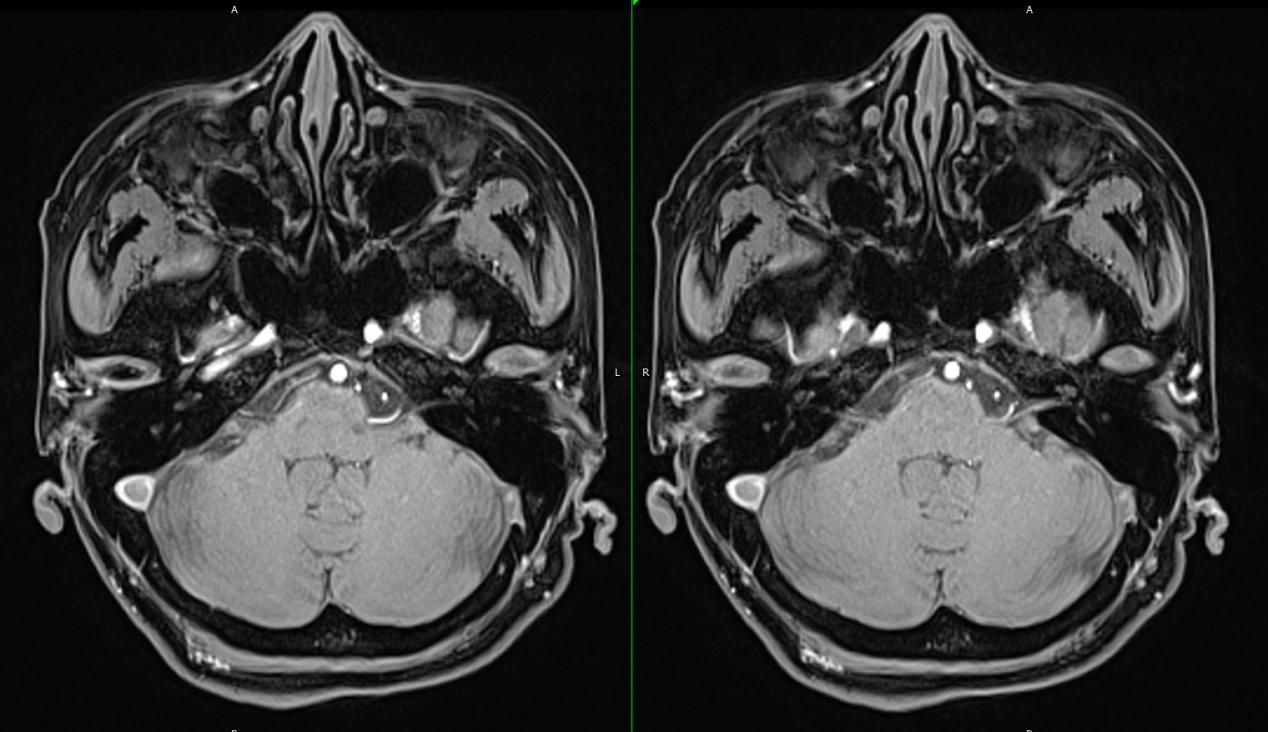

蔡医生在门诊看到彭女士的时候,第一印象是憔悴,耳鸣困扰、睡眠不足让彭女士看上去比实际年龄还苍老几岁。听了彭女士的主诉后,蔡医生让其去做面听神经MR检查,结果提示听神经有血管伴行和压迫。这下,困扰彭女士许久的耳鸣终于找到病因了,就是听神经压迫。为了解除听神经压迫,蔡医生建议彭女士做听神经微血管减压术,彭女士和家人商量后,同意手术。

微血管减压术不用大开颅,只需在患者耳后切口,开一小骨孔开颅,把仪器探进去,进入桥脑池找到听神经。在显微镜下可见小脑前下动脉行走于面听神经之间并压迫听神经,蔡医生将这根血管移开并在听神经与血管之间植入薄层垫片,这个手术就完成啦。

耳鸣的原因多种多样,多数为内耳道病变或听神经病变所致,找到病因后就可以对症治疗。但是有一类耳鸣病人,内耳或颅内的各项检查都未能发现病变,普通的治疗无效,就跟彭女士一样。这个时候就应该考虑是否存在血管压迫听(耳蜗)神经的可能,做一个面听神经的磁共振(MR)即可发现问题,而且这类患者常表现为高频耳鸣或高频混合低频耳鸣,伴有波动性、缓慢进展的听力下降,有些病人还伴有位置性眩晕。